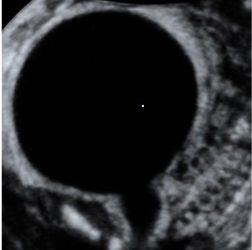

How To Do Marzo 2024: malformazioni uterine

Cari soci, questo mese un nuovo video "How to do", dedicato allo studio ecografico delle malformazioni uterine. Grazie a Ilaria...